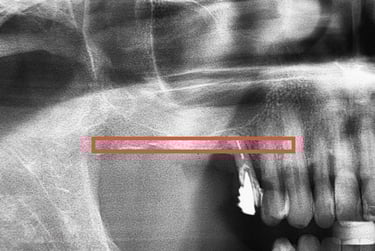

O planejamento da cirurgia dos dentes do siso normalmente é realizado por meio de tomografias computadorizadas. Elas permitem visualizar com precisão a localização do canal mandibular (seta), cuja lesão durante a cirurgia pode causar complicações neurossensoriais e hemorragias, reforçando a importância de um bom planejamento cirúrgico.

Esse planejamento detalhado também possibilita desviar de estruturas importantes, como o canal mandibular (por onde passa um nervo sensível) e o seio maxilar (uma cavidade natural próxima aos dentes superiores), tornando o procedimento mais seguro e previsível.